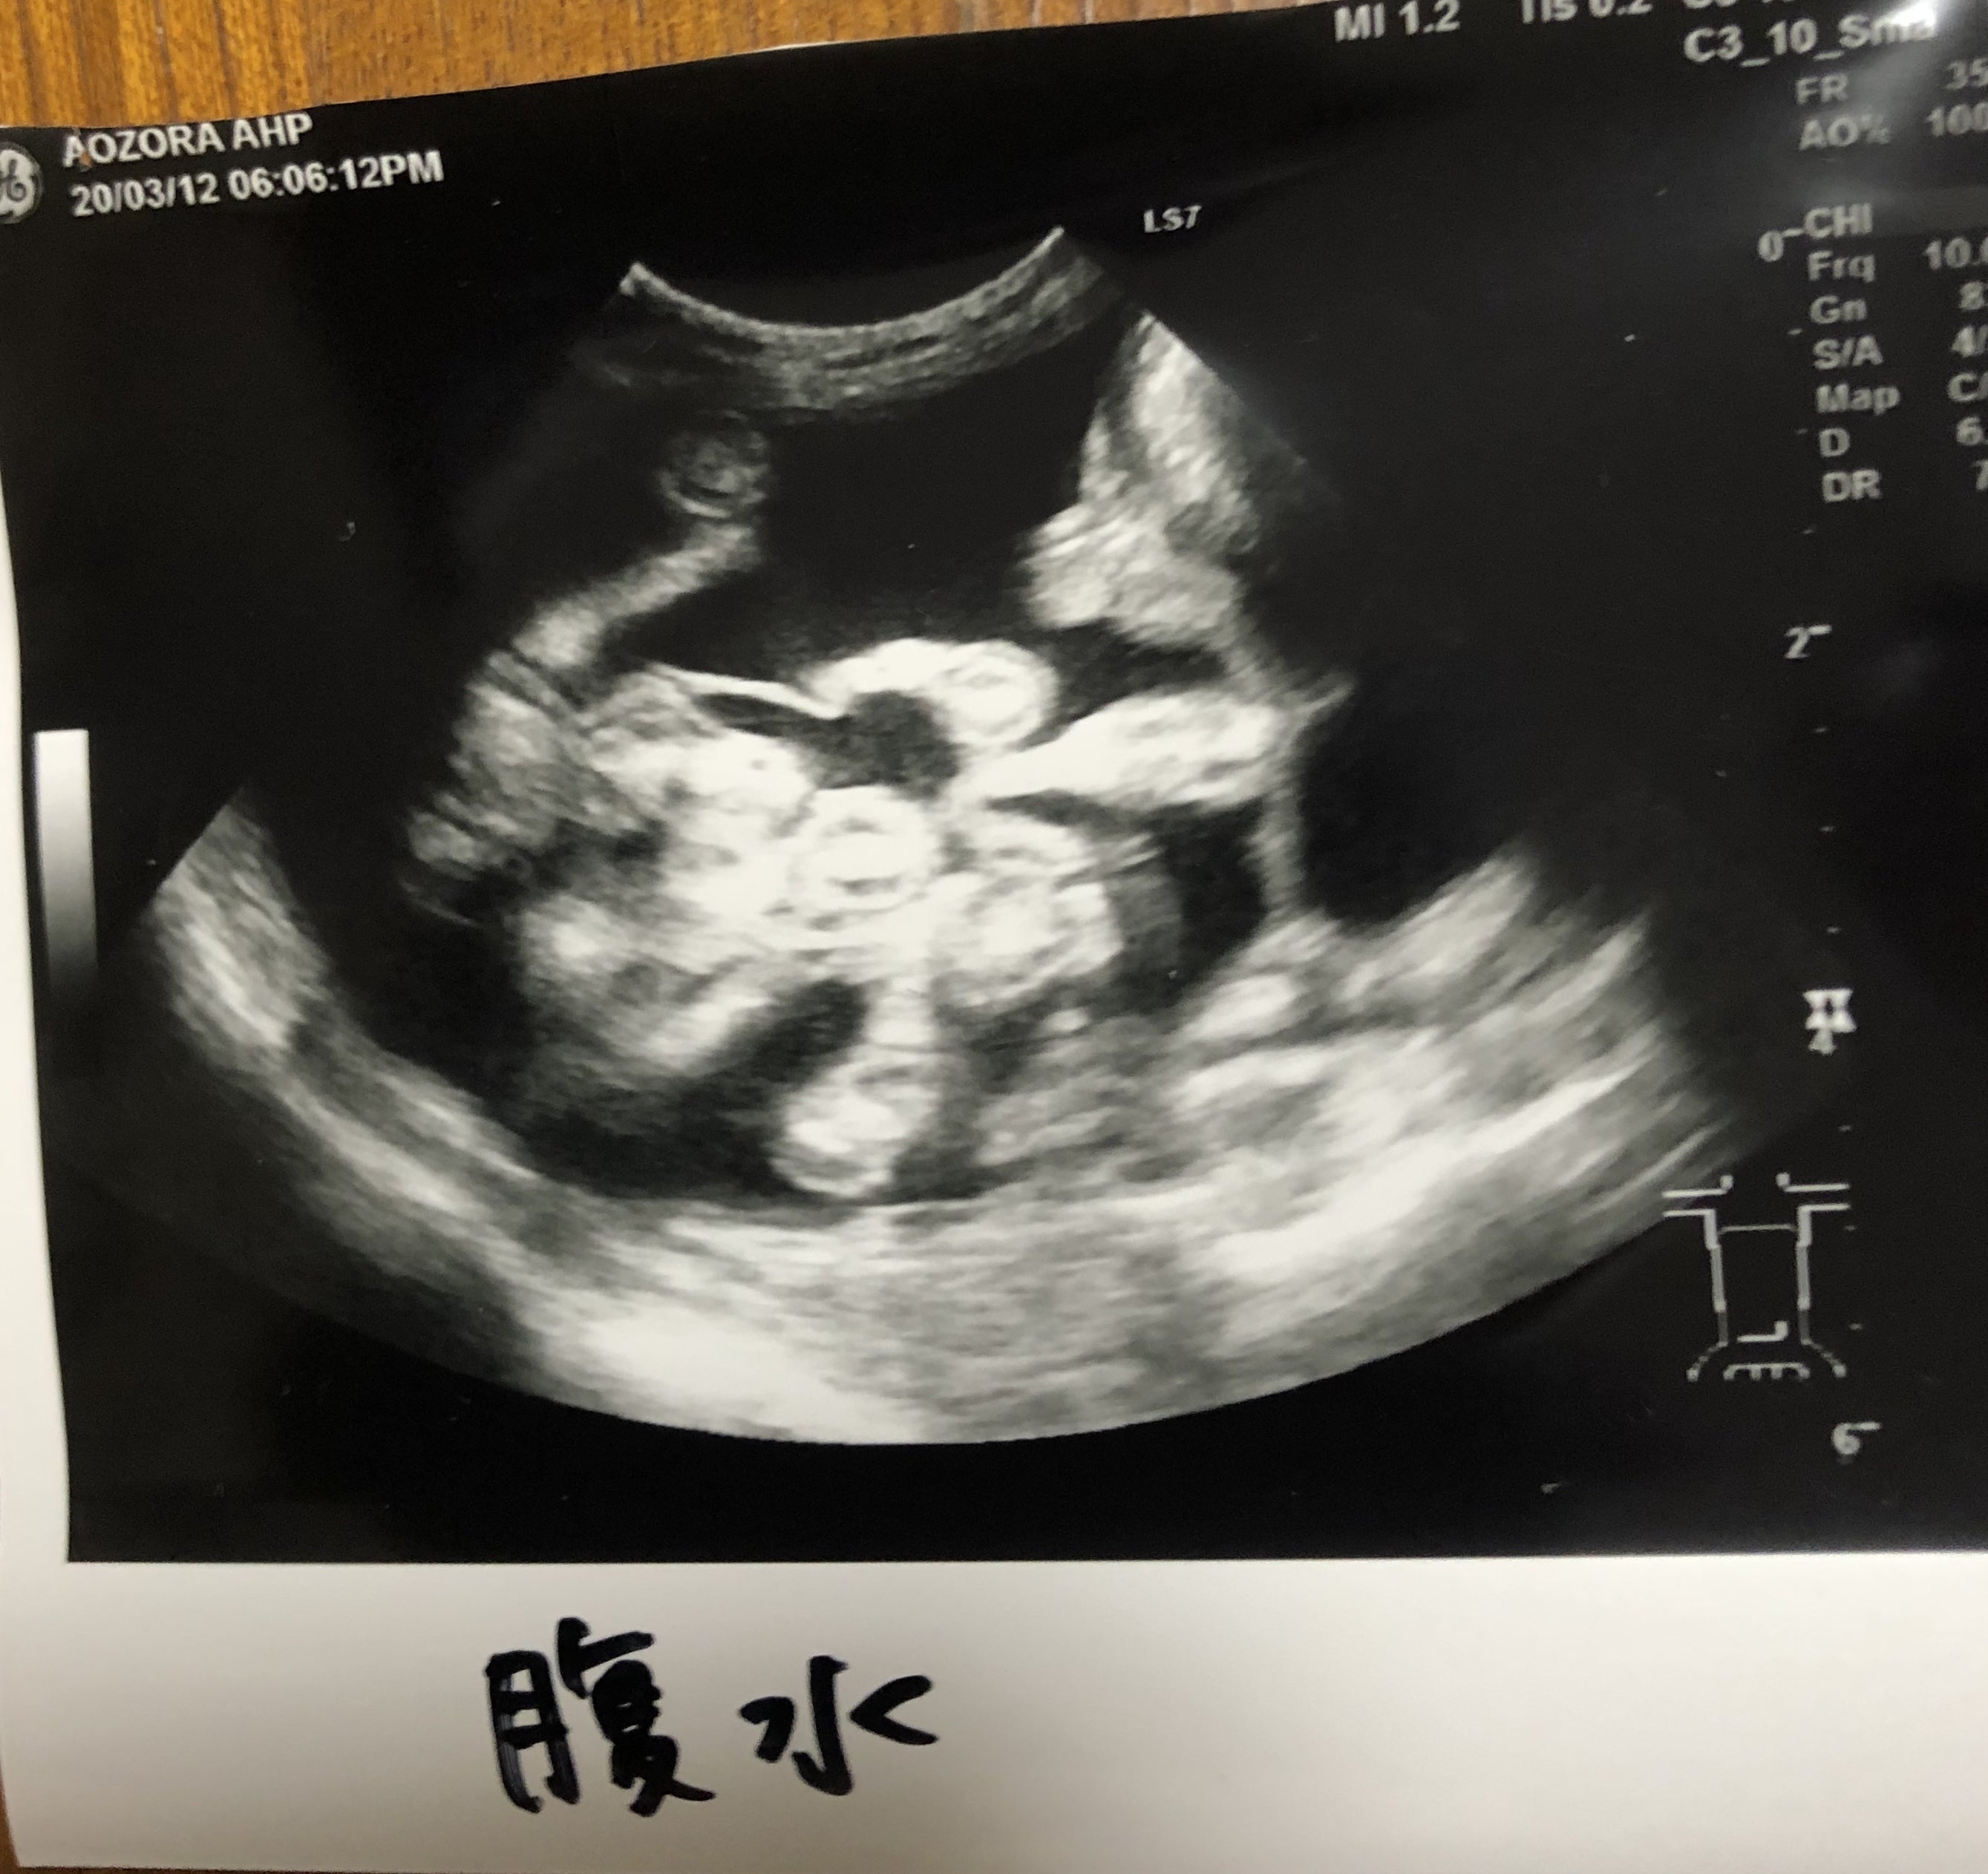

去年12月の去勢手術の際の検査では 何も問題が無かったのに、突然の発症でした。最初の病院では、ステロイド等などの治療では 回復が望めないという診断でした。こんなに愛らしく甘えてくれるポテトを どうしても助けたい一心で 藁にもすがる思いで情報を探しに探して、やっとたどりついたのがMUTIANでした。すぐに協力病院で診察していただき、ポテトは ウェットタイプの中期と診断されました。症状は高熱、貧血、下痢、食欲不振、そして 腹水が溜まり ポテトは とても辛いはずだと先生に言われました。